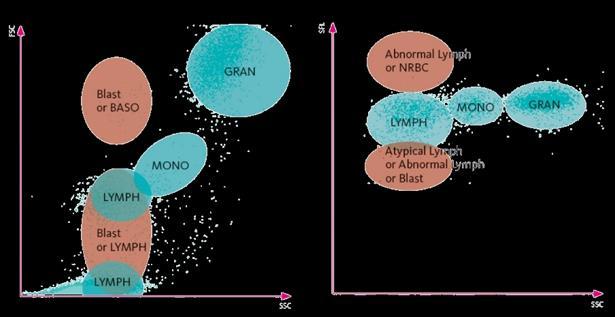

CÉLULAS PRECURSORAS DE LEUCOCITOS

El canal WPC (White Precursor Cells) es una modificación del análisis para realizar el diferencial leucocitario (XN-DIFF) en el que usando el mismo procedimiento se varían las concentraciones de polimetina y etilenglicol y se utiliza etanol en lugar de metanol para obtener una clasificación diferente. Este análisis se utiliza principalmente ante la presencia de alarmas de Atypical Lymph, Abnormal Lymph o Blast. En la primera etapa de la reacción el agente de lisis actúa sobre los lípidos y por tanto el contenido lipídico de la membrana determina la perforación celular y posterior entrada de los fluorocromos.

De esta manera, detecta linfocitos anormales, monocitos anormales y blastos, así como granulocitos anormales. Las membranas de los linfocitos anormales tienen un mayor contenido lipídico, por lo que se unen más fluorocromos y por tanto aumenta la Side-Fluorescence Light, separando a esta población de los linfocitos normales. Por otro lado, los blastos presentan baja fluorescencia debido al bajo contenido lipídico de la membrana. Combinando la información del tamaño celular, la complejidad intracelular y la intensidad de fluorescencia, podemos mejorar la identificación de estas poblaciones patológicas. La separación se puede observar en la Figura 5. Un ejemplo del uso de este parámetro lo encontramos en la Figura 6a. En el gráfico WDF destaca una población de monocitos con alta fluorescencia (4,67 x 103 células/uL) junto a una bicitopenia (8,3 g/dL de hemoglobina y 19 x 103 plaquetas/uL) en una paciente de 69 años con valores previos normales. En el gráfico de WPC destaca una población separada de células que presenta baja fluorescencia. Al revisar el frotis de sangre periférica (Figura 6b), observamos gran cantidad de células blásticas de tipo mieloide con un signo característico de huella dactilar. Esta anomalía morfológica corresponde a una mutación en el gen de la Nucleofosmina, lo que determina una entidad clasificada por la World Health Organization (WHO) como AML with mutation in NPM1 gene. El workflow del propio analizador realiza un re-test por WPC en el caso de encontrar una linfocitosis absoluta o la aparición de una alarma Blast/Abnormal Lymph. En nuestro caso, ante una linfocitosis > 5 x 103 células/uL en adultos o >

Figura 5. Scattergramas del canal WPC de Sysmex. Adaptado de Jones AS, 2015